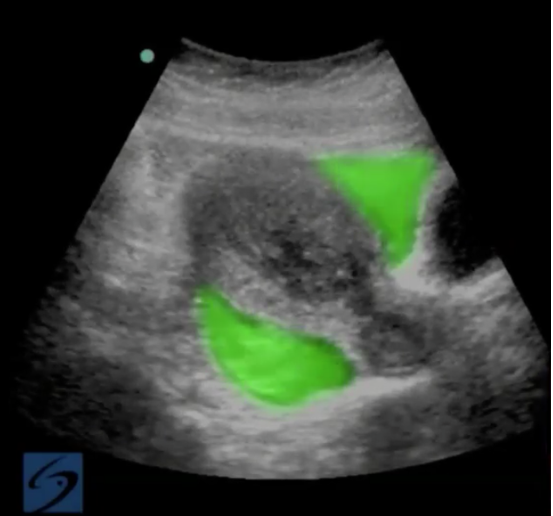

強調表示されたイメージの骨盤子宮外妊娠の破裂

強調表示された領域: 子宮外妊娠の破裂